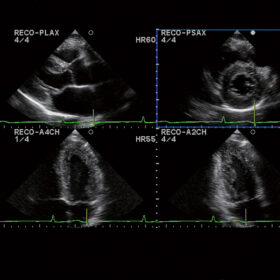

Ultrasound Aloka Prosound Alpha 6 – Image Gallery and Videos

Cardiovascular

ProSound 6 offers a full complement of various analyzing software. Dual Dynamic Display (D.D.D.), Free Angular M-mode (FAM), and Doppler Auto Trace make daily examinations more comfortable. Software such as Asynchrony Study, Tissue Doppler Imaging (TDI), Strain, eTRACKING provide more detailed, quantitative evaluation. The ProSound 6 is ready for the fundamentals and more.